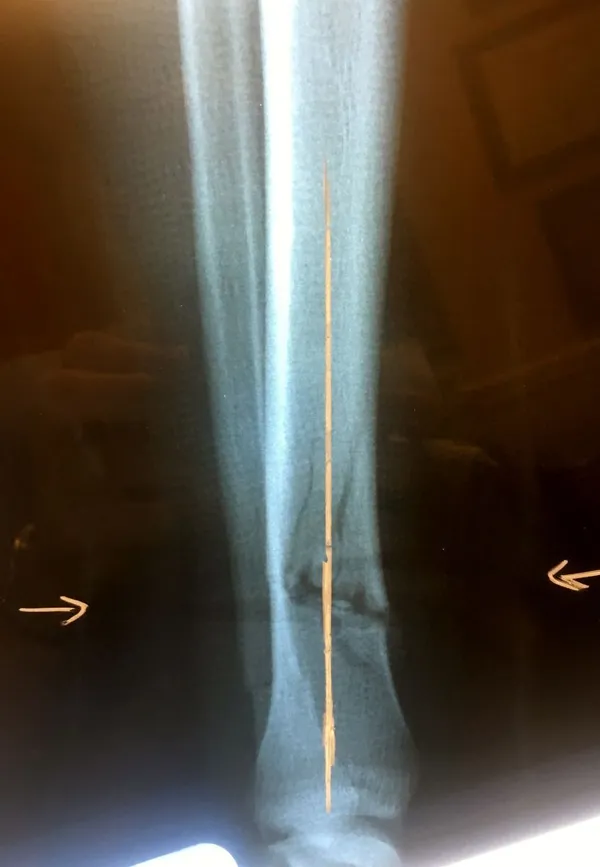

Below, Tibia and Fibula Fracture in a 16 year old injured skiing. The patient presented to the office 8 days after injury with a displaced fracture. The first 2 films show the displacement in the fracture of the tibia. After an above knee cast is appiled, the cast is wedged under fluoroscopy and new xrays show the near perfect reduction of the fracture. The white arrows show the area where the cast is wedged

Wedging of cast to keep a tibia fracture well aligned. We wedge the cast on a side if there is malalignment early on in the fracture healing to realign the fracture